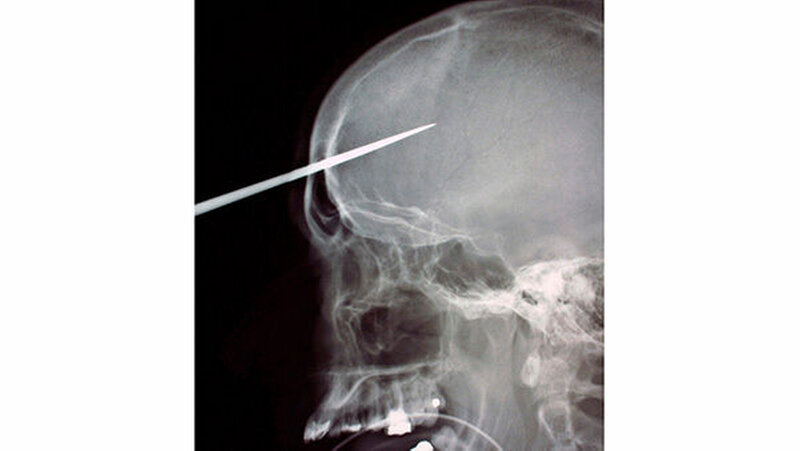

Fremdkörper im Gesicht

Vom Bohrer im Kopf bis zum Schlüssel in der Kieferhöhle: Die MKG-Chirurgen der Charité haben ausgewählte Patientenfälle mit Fremdkörpern im Gesicht zusammengestellt. In unserer Fotostrecke finden Sie die eindrucksvollen Aufnahmen.